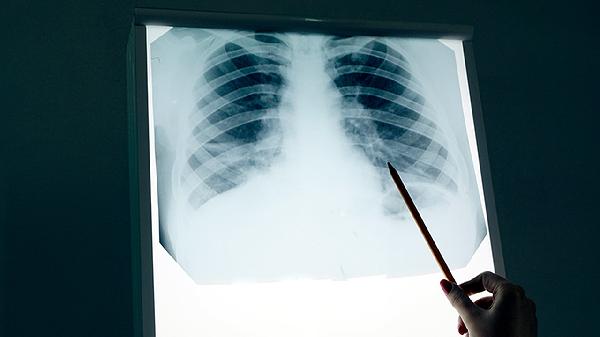

肺癌放疗后可能出现放射性肺炎、放射性食管炎、放射性皮炎、骨髓抑制和心脏损伤等并发症。放疗是肺癌治疗的重要手段,但可能对周围正常组织造成损伤,需密切监测并及时处理。

放射性肺炎是肺癌放疗后常见的并发症,通常在放疗后1-3个月出现。患者可能出现咳嗽、胸闷、气短等症状,严重时可导致呼吸困难。放射性肺炎的发生与放疗剂量、照射范围等因素有关。治疗上可遵医嘱使用醋酸泼尼松片、氨溴索口服溶液等药物缓解症状,必要时需进行氧疗。